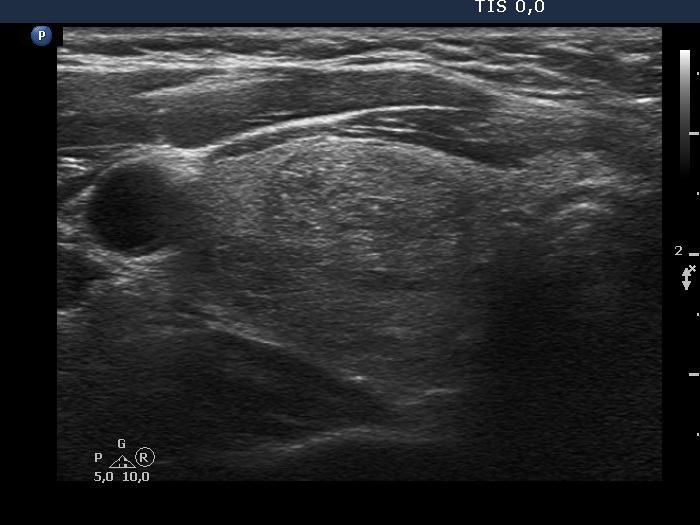

Ultrasonography. The thyroid was echonormal and had multiple nodules, mostly minimally hypoechoic or echonormal. The dimensions of the left lobe were 27x15x57 mm (12.1 mL in volume). This lobe had a minimally hypoechoic-echonormal nodule which presented halo sign. The dimensions of the nodule were 22x13x53 mm (7.93 mL in volume). Compared with the first examination for 17 years, the volume of the nodule increased by 23% while the nodule did by 43.9%. (The height of the patient was 168 cm, the weight was 86 kg.)